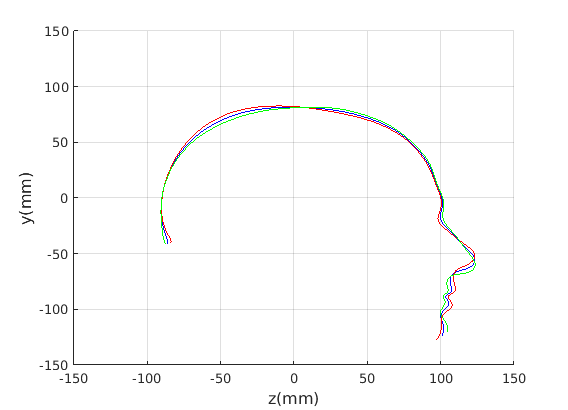

For the cranial sagittal profile model, when not scale-normalised (Fig. 20, left column), the following dominant shape modes are observed:

-

1.

Cranial height variation with a low correlation with cranial length.

-

2.

Cranial length variation with a low correlation with cranial height.

-

3.

A cranial bulge that varies between the front and rear of the cranium.

-

4.

This mode picks up minor variations on cranial shape and some noise where hair exits from the latex cap.

When data is scale normalised (Fig. 20, right column), cranial height and length are more significantly correlated, as shown in the first mode (top right in figure). The second mode model a bulge that can vary from the front to the rear of the cranium. Taken together, these two modes capture close to 90% of the variation in the training set. A two-dimensional model, based on these two modes is used in a clinical case study in Sect. 8.